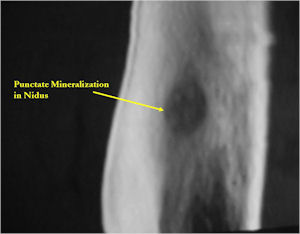

CT Scan:

- Well defined nidus with a smooth peripheral margin; +/- mineralization (CT more sensitive than XR and MRI for detecting mineralization); CT is better for detecting nidus in presence of exuberant sclerosis

- Lucent nidus surrounded by a zone of marked sclerosis

- The nidus may demonstrate mineralization/ossification usually from the center outward that appears as a central zone of density within the nidus